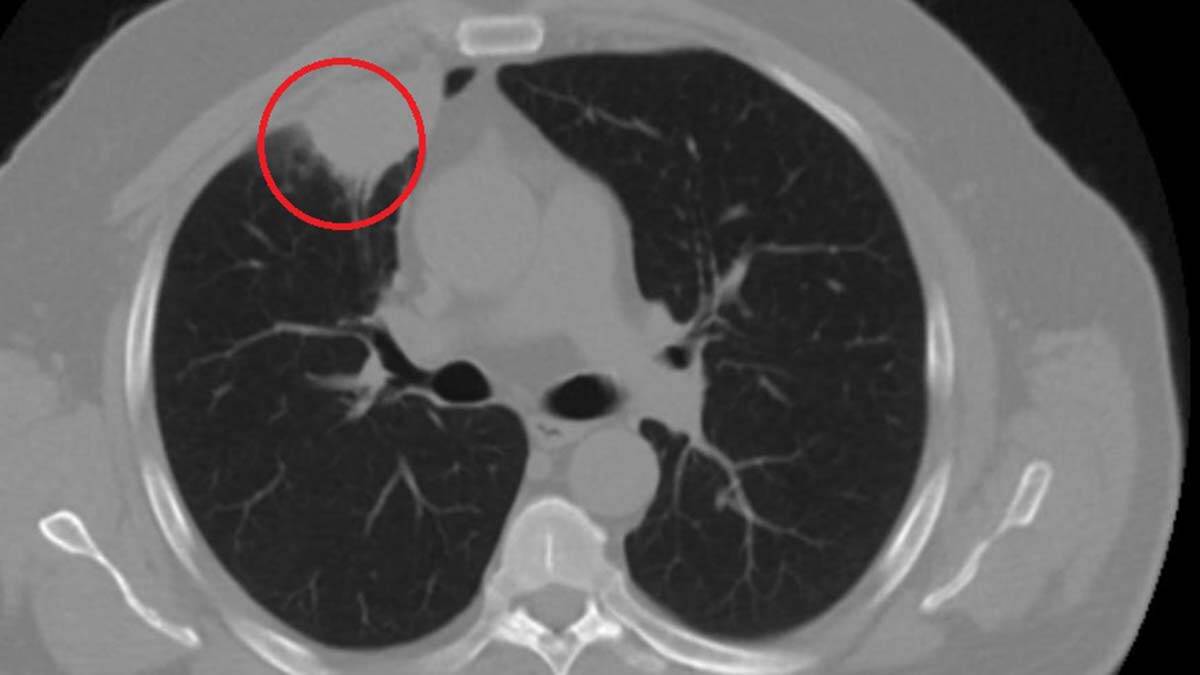

Kent dışında çalışan N.T.’nin, göğüs ağrısı şikayetiyle gittiği hastanede çekilen tomografisinde sağ akciğerinde 4 santimetre çapında tümör tespit edildi. Kanser olabileceği şüphesiyle yapılan ileri tetkikler sonrası N. T.’ye akciğer kanseri teşhisi kondu ve acil ameliyat kararı verildi. Bunun üzerine N.T., ameliyat için memleketi Kahramanmaraş’a geldi. Sütçü İmam Üniversitesi Sağlık Uygulama ve Araştırma Hastanesi Göğüs Cerrahi Anabilim Dalı Öğretim Üyesi Dr. Fatoş Kozanlı da tomografi ve test sonuçlarına göre N. T.’ye akciğer kanseri teşhisi koydu ve ameliyat yapılması gerektiğini söyledi.

“Hastamız, çalıştığı başka bir kentte göğsünden darbe alıyor ve ağrıları geçmeyince bir üniversite hastanesine başvuruyor. Burada hastaya bir akciğer grafisi çekiliyor. Sağ akciğerinde bir kitleye rastlanıyor. Daha sonra hastaya, bir akciğer tomografisi çekiliyor ve göğüs cerrahisi için önemli büyüklükte olan 4 santimetre çapında, akciğer kanserine benzer özellikte radyolojik bulgular olan bir kitle tespit ediliyor.

Daha sonra hastaya yapılan ileri tetkiklerde akciğer kanseri teşhisi konuluyor. Hastaya bir cerrahi planlanıyor. Hasta Kahramanmaraşlı olduğu için kendi memleketine gelmeyi tercih ediyor. Bize başvurdu ve göğüs ağrısı şikayeti vardı. Öksürük, nefes darlığı, balgam çıkarma, ateş gibi şikayetleri yoktu. Hastayı biz de değerlendirdik ve ameliyat olmasına karar verdik. Çünkü akciğer kanserine çok benzer radyolojik bulguları vardı. Sağlık Bakanlığımızın kuralları gereği her hastayı ameliyat öncesi PCR testi yapılır. Biz de ameliyat gecesi hastadan PCR testi aldık ve testi pozitif geldi. Ameliyatımızı 14 gün erteledik ve hastamıza koronavirüs tedavisi uygulandı. Hasta 14’üncü gün tekrar bize başvurdu ve yapılan PCR testi negatif çıktı.

Yeni bir tomografi çektik ve tümörün tamamen ortadan kalktığını gördük. Şimdi sonuç bilgilerinden başlangıca gittiğimizde, bu bir akciğer kanseri olsaydı, ortadan kalkması mümkün değildi. Başka bir patolojiye bağlı durum olsaydı, yine verdiğimiz tedaviyle ortadan kalkmasını çok beklemeyiz. Antiviral tedavisi verdik ve hastanın radyolojik bulguları neredeyse tamamen normale döndü. Hastaya bunu izah ettik, ‘Dünya literatüründe hiç görülmeyen bir radyolojik bulgu’ diyerek. Bu gördüğümüz manzara artık hastanın akciğer grafisinde yok, akciğer kanseri değil. “